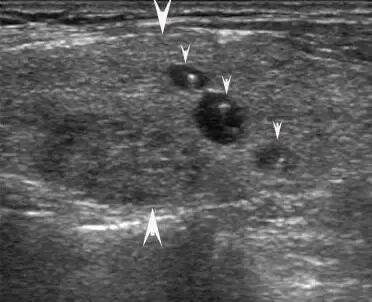

大箭头指向腺体,小箭头指向结节,结节外腺体回声不均

大箭头指向腺体,小箭头指向结节,有的结节伴弧形钙化,结节外腺体回声不均。